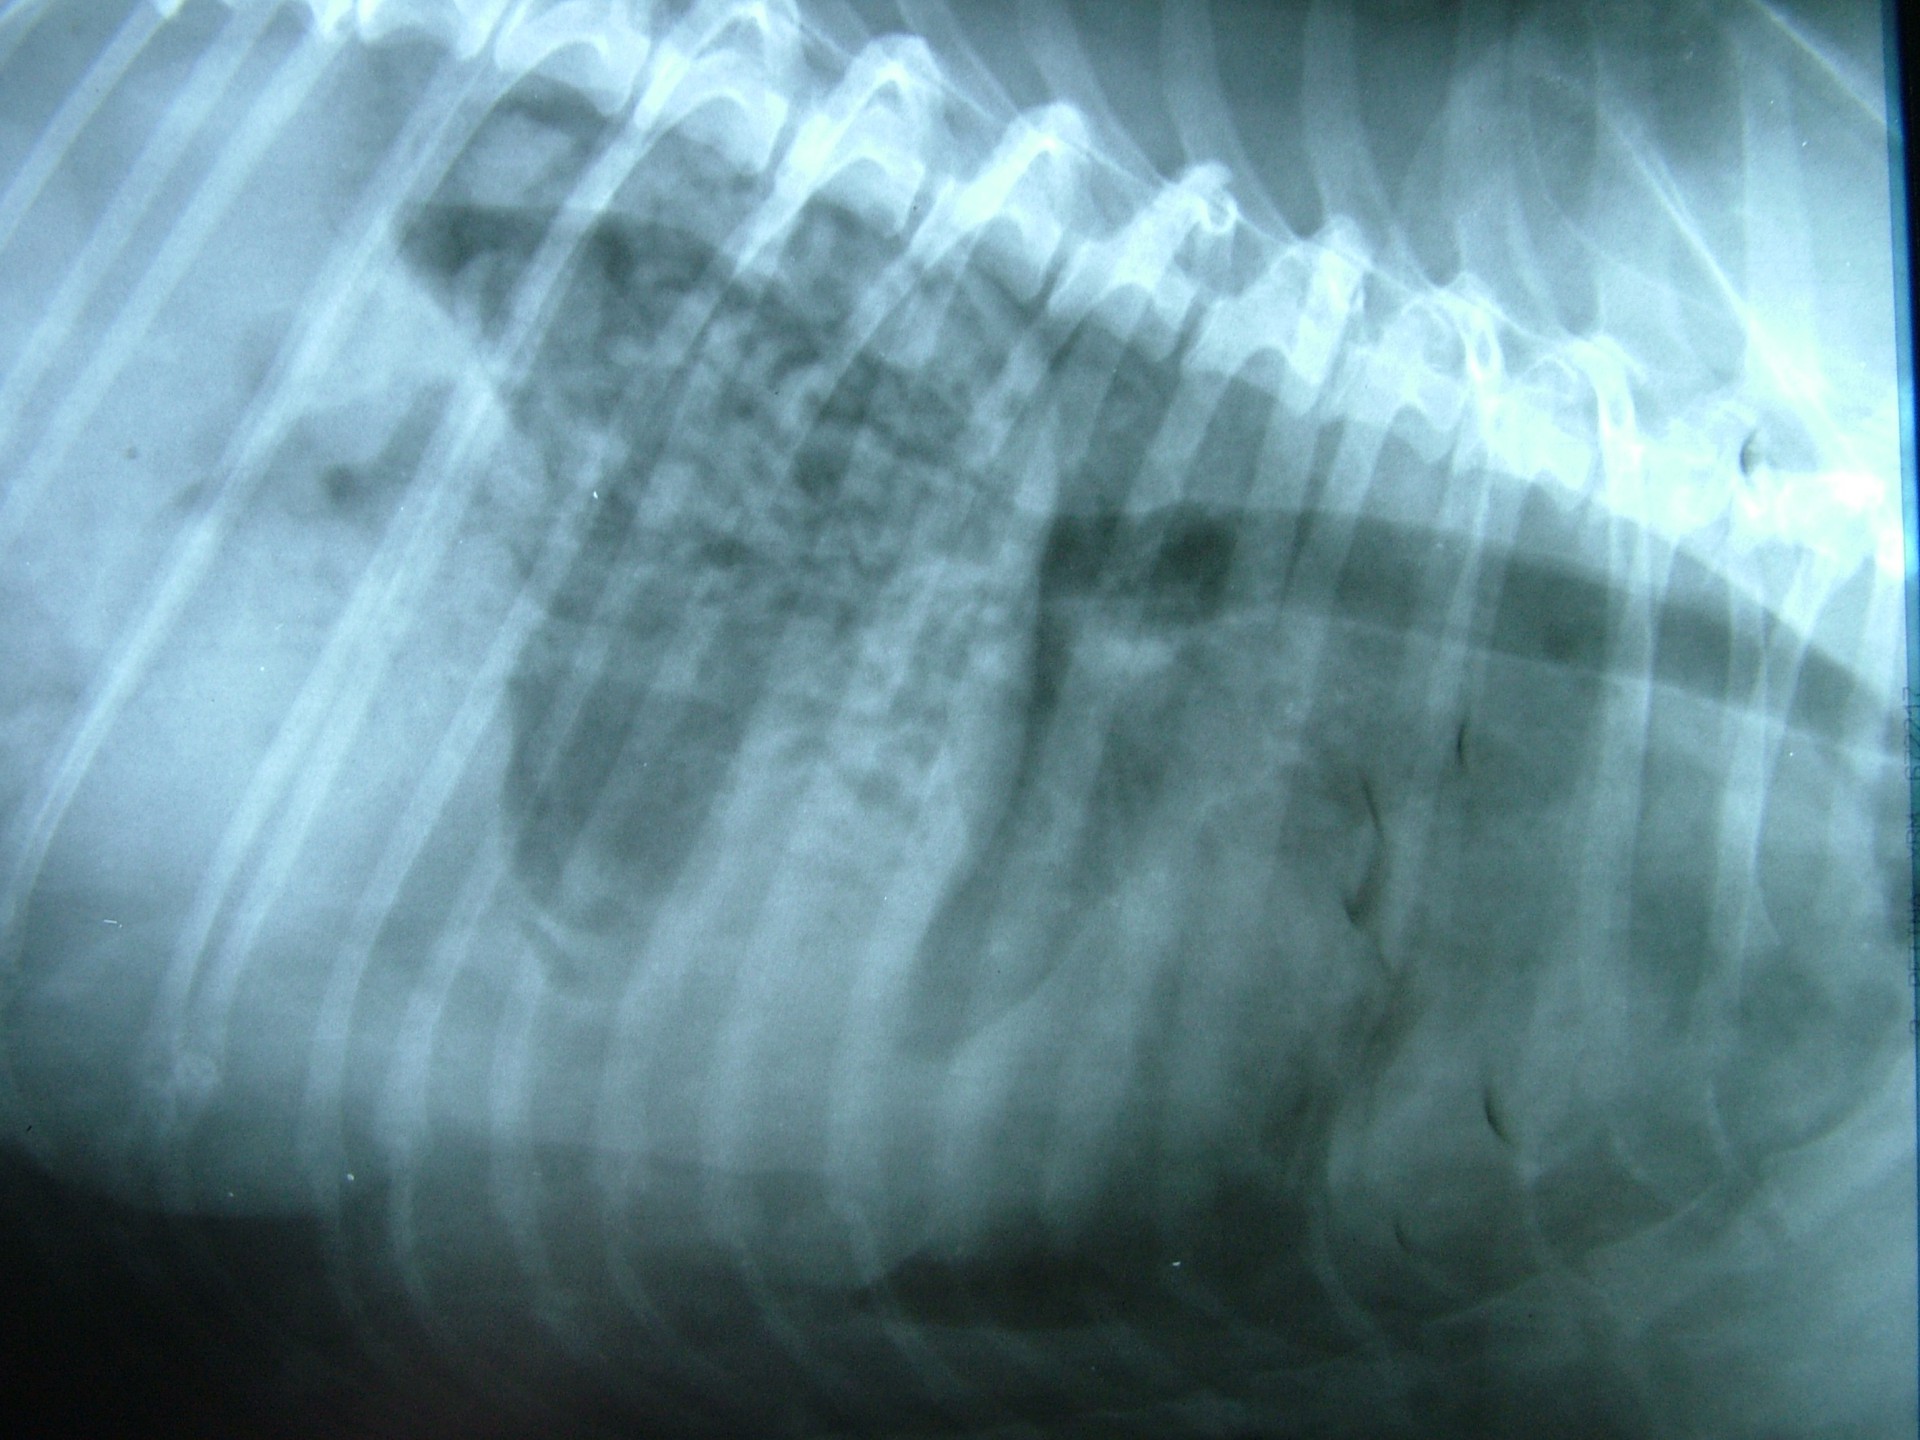

• A traumás eredetű rekeszsérv (hernia diaphragmatica traumatica) minden esetben valamilyen sérülést követően alakul ki. A rekesz folytonossága a sérülés következtében megszakad és az így kialakult sérvkapun keresztül a hasüregi szervek a mellüregbe előesnek. A betegség kórjóslata a trauma következtében kialakuló egyéb szervi sérülések miatt (máj-, léprepedés, tüdőzúzódás stb.) kifejezetten rossz. Az esetek döntő többségében az állatok súlyos általános állapotban kerülnek a rendelőbe, a diagnózis felállítását és a vérkeringés stabilizálását követően a traumás eredetű rekeszsérv azonnali műtéti ellátást igényel.

Mindhárom rekeszsérv forma meglehetősen ritkán fordul elő. A diagnózis felállítása a kórelőzmény, a klinikai tünetek a mellkas röntgenvizsgálata, a hasüreg ultrahangos vizsgálata alapján lehetséges.A rekeszsérv műtéti ellátása során a legnagyobb kihívást az jelenti, hogy a hasüreg megnyitását követően a sérvkapun keresztül levegő kerül a mellüregbe, ezáltal az állat spontán légzése leáll, így a műtét teljes ideje alatt asszisztált lélegeztetésre van szüksége.A műtét során a mellkasba előesett szerveket reponáljuk, a rekesz folytonosság hiányát megszüntetjük és a mellkasban lévő szabad levegőt eltávolítjuk, ezzel biztosítva az állat spontán légzését. A műtétet követő napokban legfontosabb feladat a vérkeringés és a légzés folyamatos, kórházi körülmények közötti kontrolálása.Az idejében felismert és megfelelően ellátott veleszületett rekeszsérv jó eséllyel gyógyítható, a traumás eredetű sérv ellátásának eredményességét általában az egyéb szervek sérülése határozza meg.